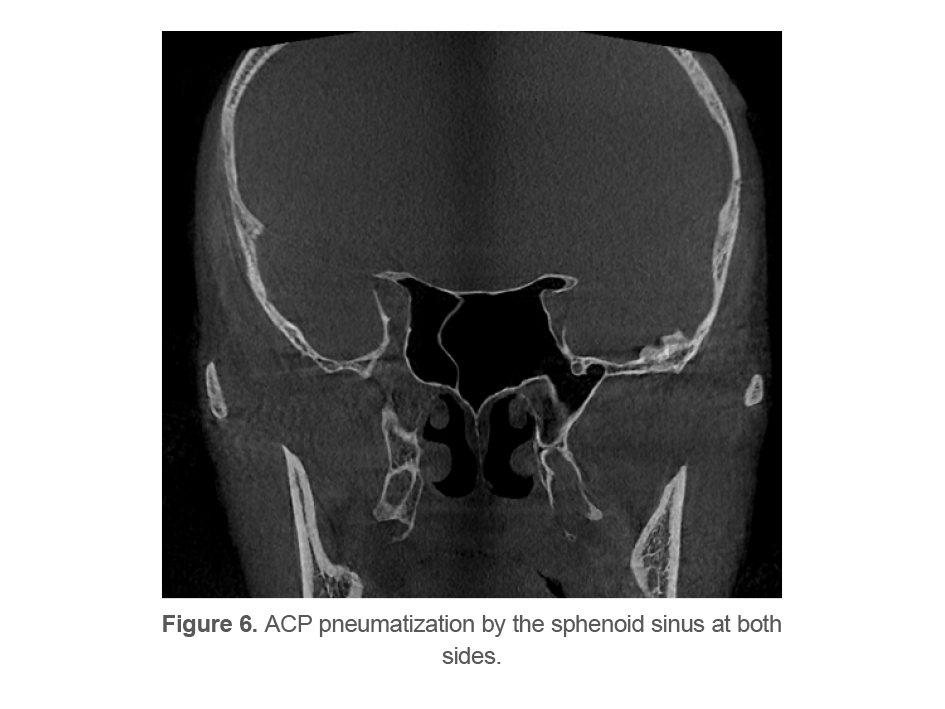

The type of pneumatization of the sphenoid sinus is determined based on the correlation of sphenoid sinus with sella turcica in the sagittal plane, which is categorized into four main types. To outline the sella turcica, two vertical lines were drawn from the most prominent anterior and posterior points of sella turcica. The four main types are as follows:

Type 1 or conchal type: Absence of sinus or very small extension of the sinus (Figure 2A).

Type 2 or presellar: The posterior wall of the sphenoid sinus is located in front of the anterior wall of sella turcica (Figure 2B).

Type 3 or sellar: The sinus is located between the anterior and posterior walls of sella turcica (Figure 2C).

Type 4 or postsellar: The posterior sinus wall exceeds the posterior border of sella turcica. Type 4 has two subtypes of a and b. In subtype a (Figure 2D), sinus pneumatization does not include the posterior clinoid process. In subtype b (Figure 2F), sinus pneumatization is so extensive that includes the posterior clinoid process (13).

Postsellar a (4a) was the most frequent type (41.3%; n=124) followed by sellar (3) type (30%;n=90), postsellar b (4b) type (17.7%; n=53) and presellar (2) type (11%; n=33). No conchal type was noted.

Regarding the sphenoid sinus pneumatization type, type 1 was not observed in any patient. The prevalence of types 2, 4a and 4b was 11, 33, 41.3, and 17.7%, respectively. In general, type 4 was the dominant type in our Iranian study population with a prevalence of 59%. In the study by Movahhedian et al (4) the prevalence of types 1, 2, 4, 4a, and 4b was 1, 11.5, 35.5, 38.9, and 13.1%, respectively; in general, 52% of their study population showed type 4. Similar to the present results, Rahmati et al (6) found no case of type 1, but the frequency of types 2, 3, and 4 was 1.9, 14.6, and 83.5%, respectively, in their study. They did not separately report the prevalence of types 4a and 4b. Özer et al (7) in Turkey reported the prevalence of types 1, 2, 3 and 4 to be 1.4, 8.3, 23.6, and 66.7%, respectively. Štoković et al (22) in Serbia suggested that type 3 was the dominant type. The frequency of types 1, 2, 3, and 4 was 2, 24, 41, and 33%, respectively, in their study. However, their study had a small sample size. Güldner et al (13)evaluated 580 Swedish patients, and reported that type 3 was the dominant type. The frequency of types 1, 2, 3, 4a, and 4b was 0.3, 6.6, 57.2, 17.9, and 17.9%, respectively, in their study. In general, type 1 was the rarest type in most abovementioned studies, similar to the present study. This finding is highly important since type 1 pneumatization of the sphenoid sinus is a contraindication for trans-sphenoidal surgical procedures (23). The dominant type in the present study was 4a, which was similar to the dominant type in the study by Movahhedian et al (4); this similarity is probably due to the fact that both studies were conducted on the Iranian population. The dominant type was type 3 in the European populations as discussed earlier. Thus, variations in this regard are attributed to racial differences.

Figure 2. Types of sphenoid sinus pneumatization: (A) Presellar; (B) Sellar; (C) Postsellar a; (D) Postsellar b.